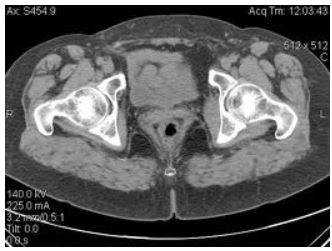

МР-скан коксофеморальных сочленений, вариант нормы

В ортопедической практике МРТ тазобедренного сустава чаще проводят для уточнения причин коксалгии - болевого синдрома в сочленении. Способ исследования не подразумевает использования ионизирующего излучения, что особенно актуально для детей и беременных женщин. Процесс создания четких снимков, которые можно увеличивать, рассматривать в объемном виде, базируется на использовании магнитного резонанса и компьютерных технологий. Для улучшения возможностей визуализации применяют контрастирование. Диагностическая ценность фото, полученных после введения гадолиния, сопоставима с результатами артроскопии - инвазивного исследования с проникновением в полость сочленения хирургических инструментов.